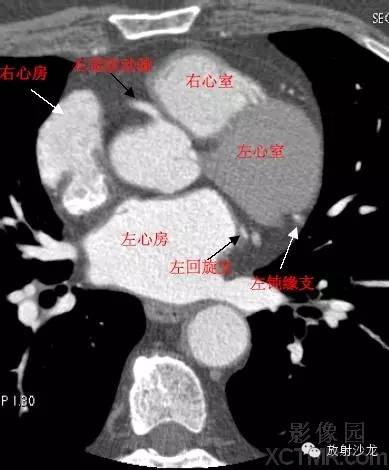

心脏冠状动脉CT解剖中文详细标注

LA -Left Atrium左心房

RA -Right Atrium右心房

LV -Left Ventricle左心室

RV -Right Ventricle右心室

LMA -Left Main Artery冠状动脉左主干

LCX -Left Circumflex Artery左回旋支

LMB -Left Obtuse Marginal Branch 左边缘支(钝缘支)